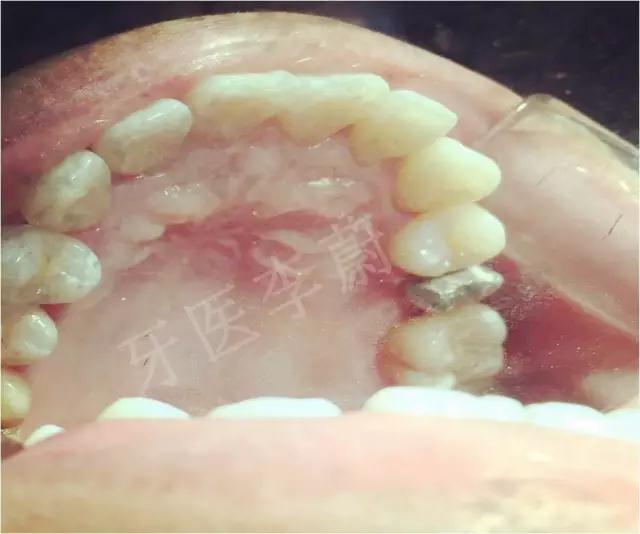

口腔检查:15冠部龋损,探及大量腐质,舌侧冠折至龈下约2mm,近、远中壁亦部分龋坏,松动Ⅰ°,叩痛(-) ,牙龈无瘘管,舌侧及近中被龈组织覆盖。

X片示:15残冠影,根尖有骨密度降低影。

临床诊断:15慢性根周炎。